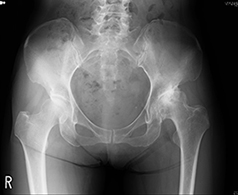

変形性股関節症

股関節は、大腿骨の骨頭と臼蓋という骨盤のくぼみからなる球関節(ボールと受け皿の関節)です。骨頭が臼蓋にはまり込む構造のため、足を様々な方向へ動かすことができます。関節の表面は軟骨に覆われ、関節のスムーズな動きを可能にしています。

加齢性の変化や外傷などにより軟骨が減少すると、すり減った軟骨の下のむき出しになった骨同士がこすれ合い、炎症が生じ痛みを感じます。

軟骨の減少により股関節の痛みが生じる疾患を変形性股関節症と呼びます。本邦における変形性股関節症の患者は約500万人とも言われ、多くの方がお悩みの疾患です。歩行中や階段昇降時の痛みや、関節の動かせる範囲が減少し靴下をはきにくい・正座ができないなどの症状を生じます。